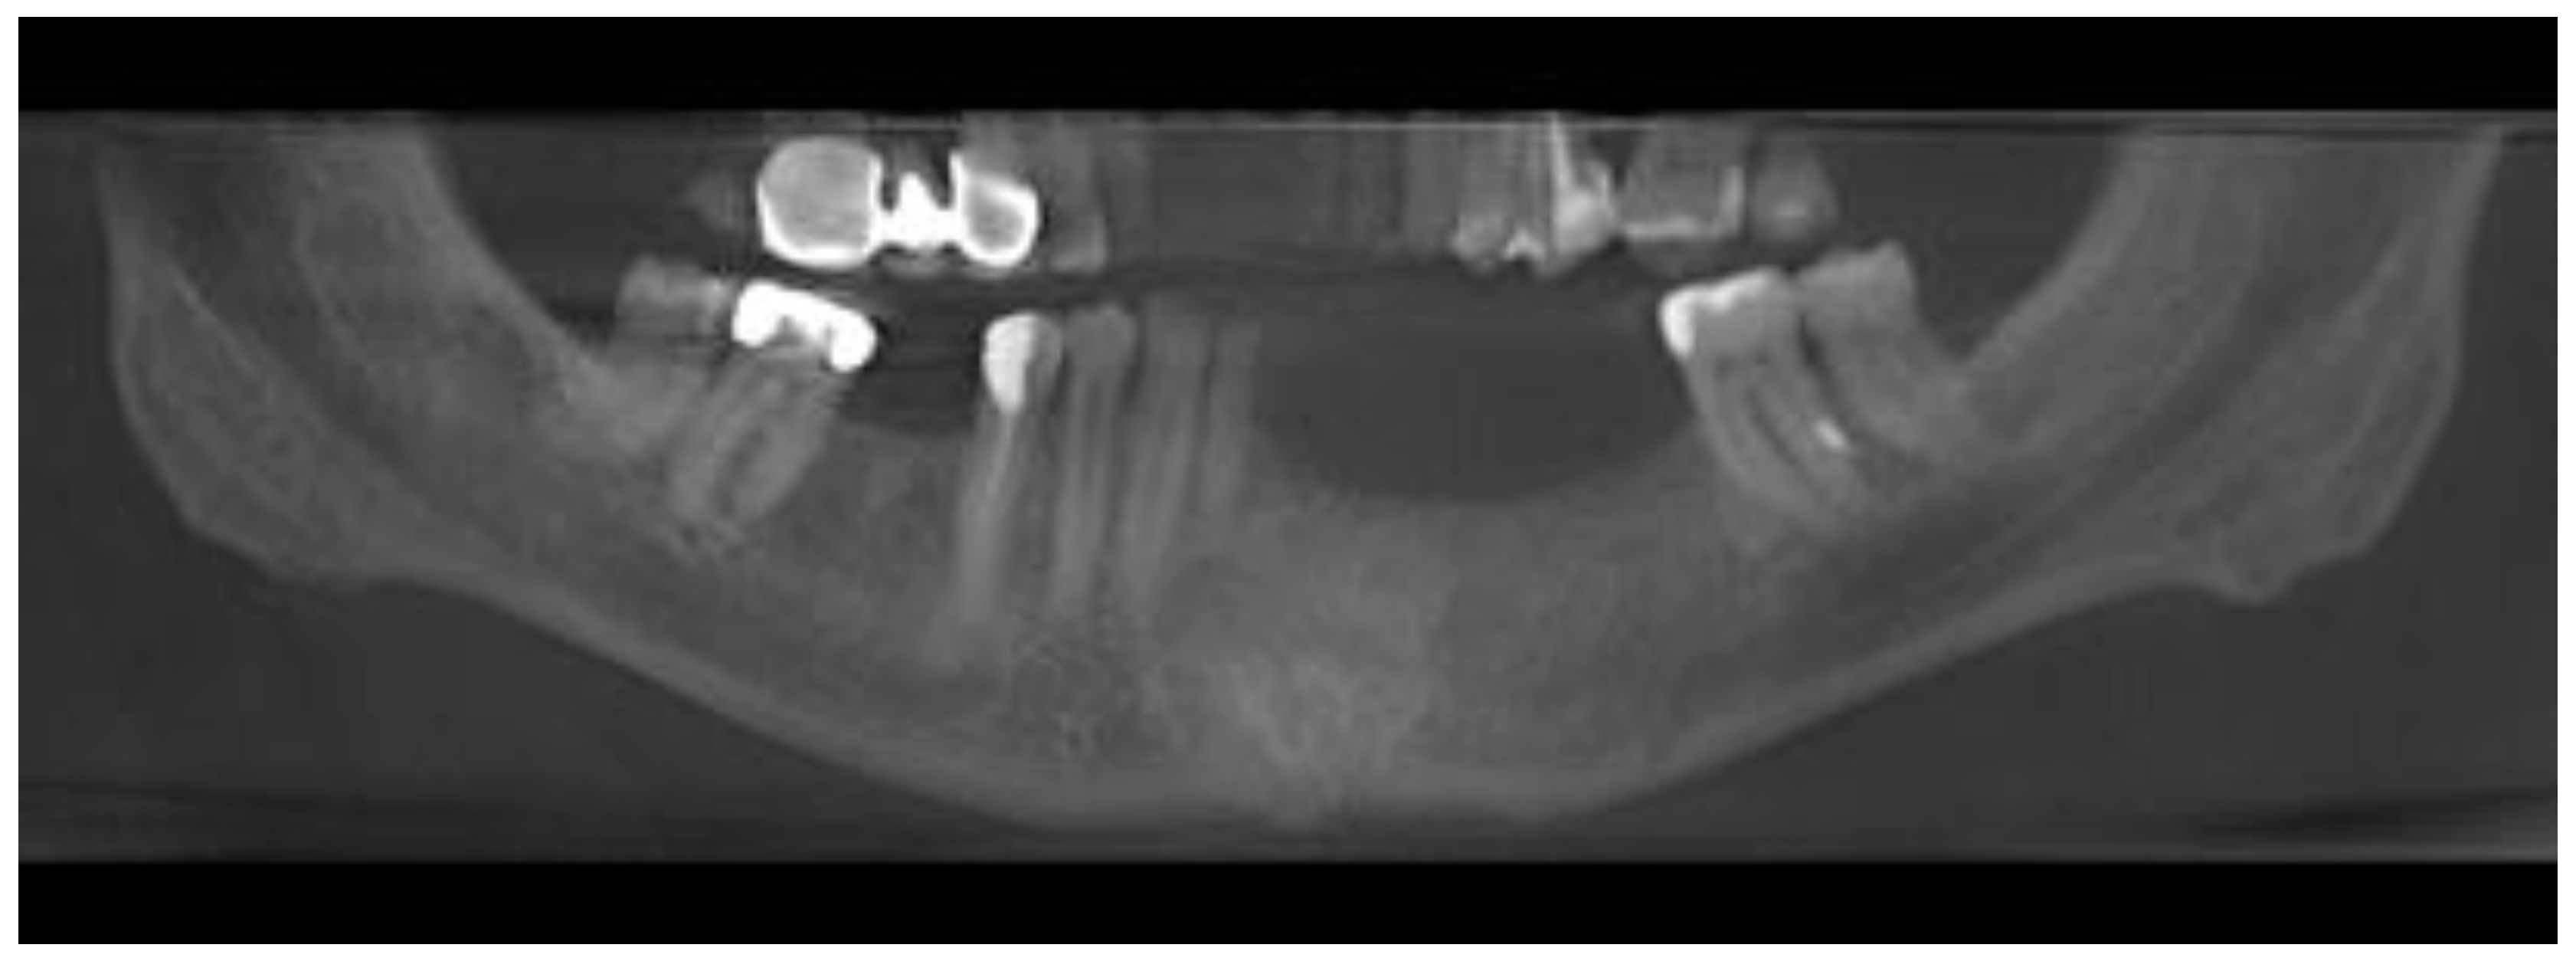

Further examination revealed extensive vestibular swelling ranging from teeth 32–35 and crepitation sign, followed by some elevation and fluctuation between teeth 33–34 (Figure 2). The mucosa was unaffected, and tenderness on the palpation was not noted. However, teeth 31–35 mobility was noted. Teeth 34 and 35 were treated endodontically by a local dentist because of the cyst. Teeth 33–43 remained vital and responsive to cold stimuli. There were no neurological deficiencies related to either cranial nerves or the trigeminal (no Vincent sign) or facial nerves (no palsy). The intraoral photograph reveals good hygiene, with some visible swelling in the anterior portion of the mandible (Figure 3 and Figure 4).

Figure 2. Intraoral photograph visualizing labial cortical swelling with crepitation and soft tissue elevation.